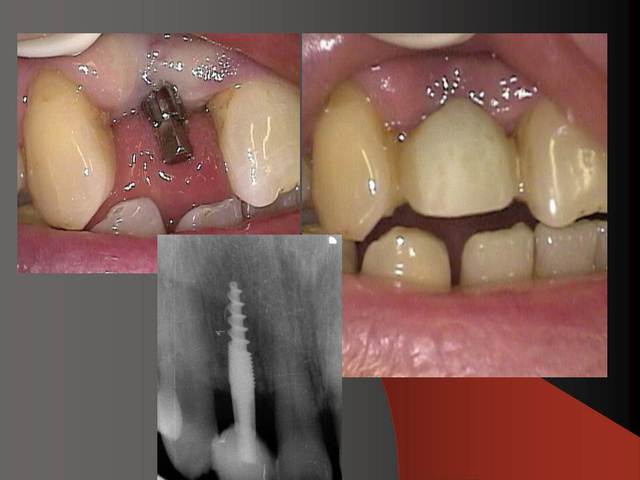

Photos d'un cas d'extraction implantation immédiate, stabilité primaire (de mémoire) assez élevée.. 60/70 N ..démontage du gingiva clips et du shuttle, pilier serré 40N, couronne procera

Merci pour le cas, bien fait. Belle présentation photo.

Le contour gingival est net, belle guérison, c'est à combien de semaine ?

Je vois un peu de ciment sur la radio finale, attention, c'est pas bien pour les tissus.

Oui je sais pour le ciment... j'utilise d'ailleur ce cas et cette radio dans une présentation pour mettre en garde sur le risque au moment du scellement de voir du ciment fuser sous la limite prothétique vers la col de l'implant..galère à éliminer...Personnellement je préfere plutot utiliser des piliers à usiner (maintenant disponibles voir shop online pour photos) au lieu des strandarts meme si il y a deux hauteurs/col implantaire en 1 et 3mm aujourd,hui disponibles..A l'époque de ce cas il n'y avait que les 1 mm et la limite est un "poil" trop profonde.

La pose de la couron nec'est faite 8 semaines apres l'extraction implantation immédiate, la particularité de ce systeme permet de ne pas démonter le shuttle ni la gingivaclip pour l'empreinte..je pense que ca aide bien à la qualité gingivale...radio controle ci jointe